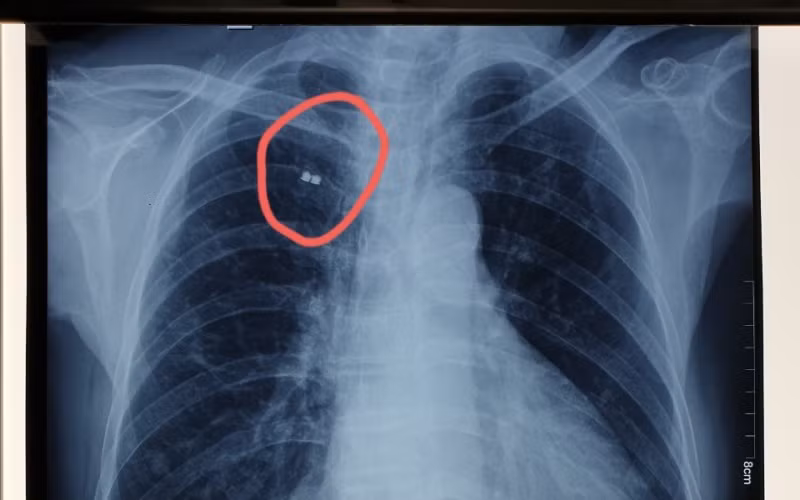

Vị trí mảnh bom trước khi gắp ra. (Ảnh: BVCC)

Khi ông N. đến khám bệnh tại Bệnh viện Xuyên Á Tây Ninh vì có một khối u sưng nề, gây đau ở vai phải; các bác sĩ đã chẩn đoán áp-xe vai phải và được tư vấn hướng điều trị là rạch tháo mủ ổ áp-xe. Bên cạnh đó, bác sĩ phát hiện có dị vật ở vùng ngực của ông qua phim chụp X-quang ngực thẳng nên đề nghị sẽ thực hiện đồng thời phẫu thuật lấy mảnh bom cho ông.

Dưới sự hỗ trợ của hệ thống C-Arm hiện đại (là hệ thống máy soi chụp X-quang và chiếu trực tiếp lên màn hình tăng sáng ngay tại phòng mổ), các bác sĩ Khoa Phẫu thuật Tim mạch - Lồng ngực xác định được chính xác vị trí mảnh bom. Ê-kíp phẫu thuật tiến hành gây tê tại vị trí mảnh bom, rạch da khoảng 2cm ở vị trí tê, bóc tách qua các lớp cơ thành ngực để tiếp cận mảnh bom nằm ở bờ dưới xương sườn số 2 trên đường trung đòn. Mảnh bom có kích thước khoảng 0,5cm đã được lấy ra dễ dàng.